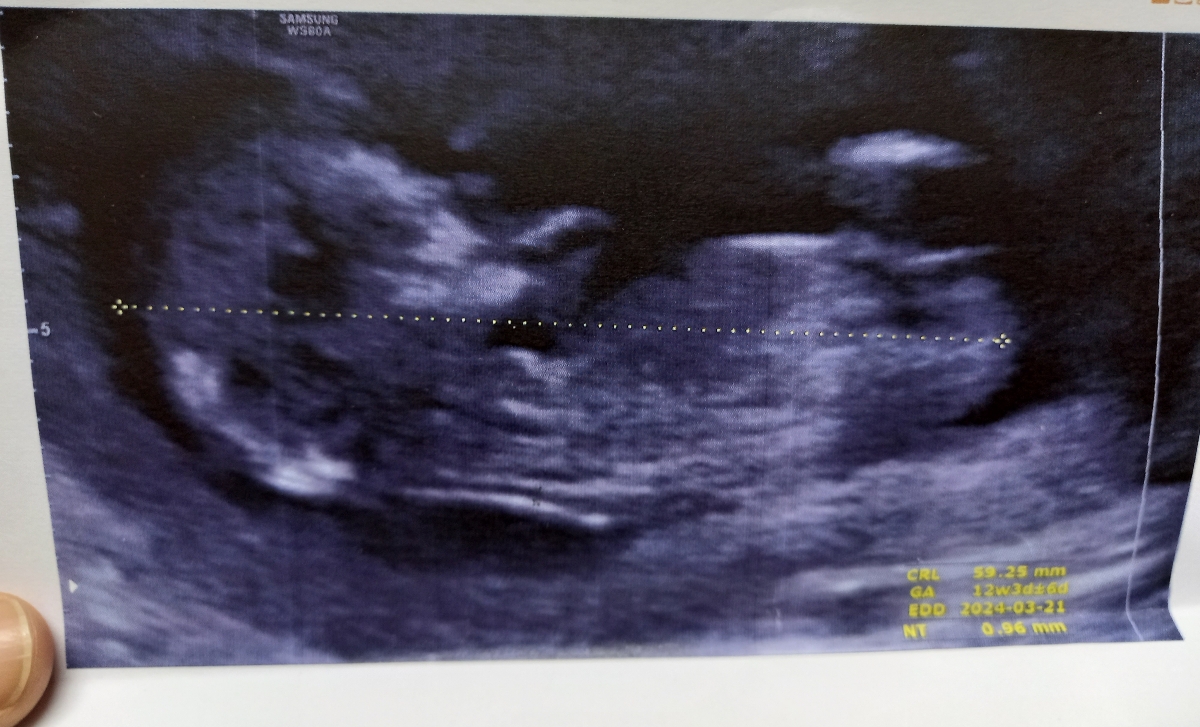

Parisa. h

اینم پسرمن😋😍

عکس سونوها رو خدا

خدا همه ی بچه ها رو حفظ کنه😍

ای جونم چند هفته رفتین برای سونو سه بعدی؟دکتر نوشت؟

سنو سه بعدی درخواست نکردم خود دکتر ک رفتم سنو ۲۴ هفته بودم گرف من نگفتم میخوام